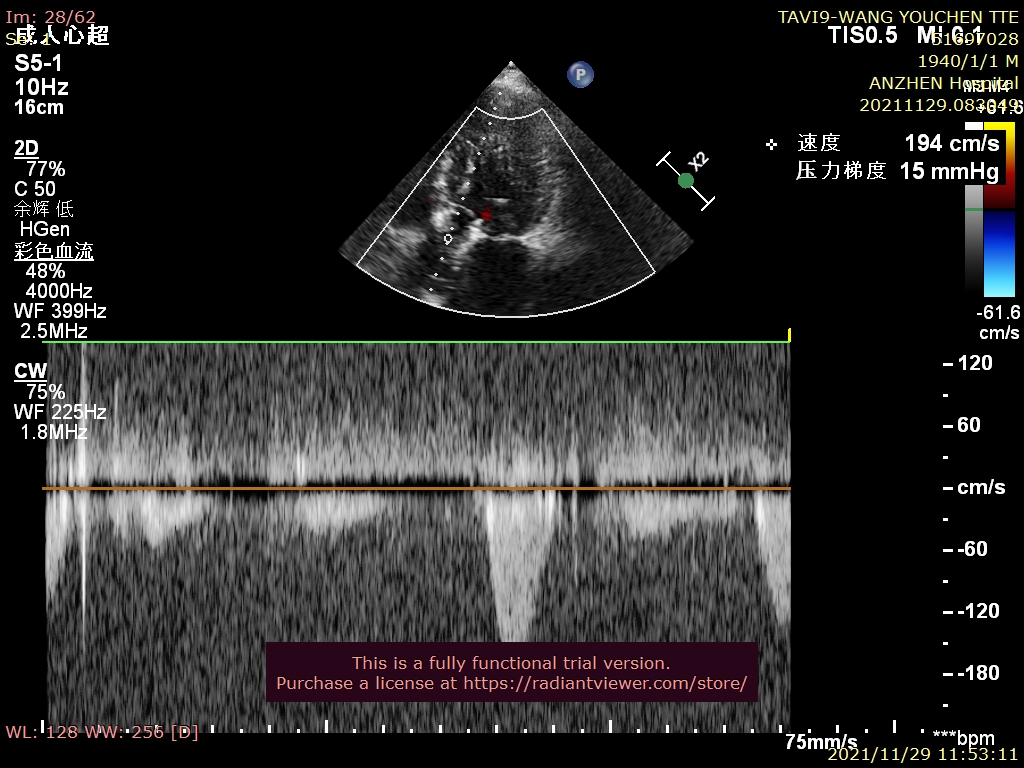

超声心动图:

平均压差60mmHg,峰值压差106mmHg,峰值流速5.2m/s,EF值 30%。

6.超声检查提示术后峰值压差15mmHg,流速1.94m/s,微量反流,患者血流动力学明显改善。